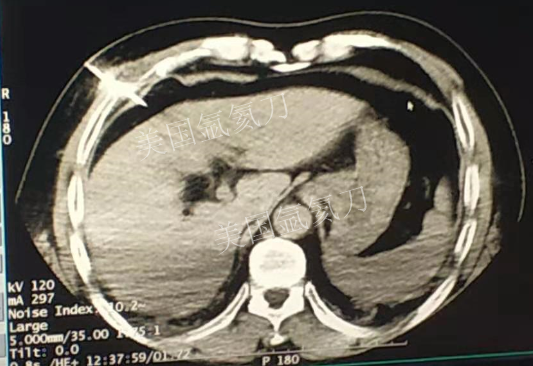

59岁男性肝部氩氦刀手术治疗